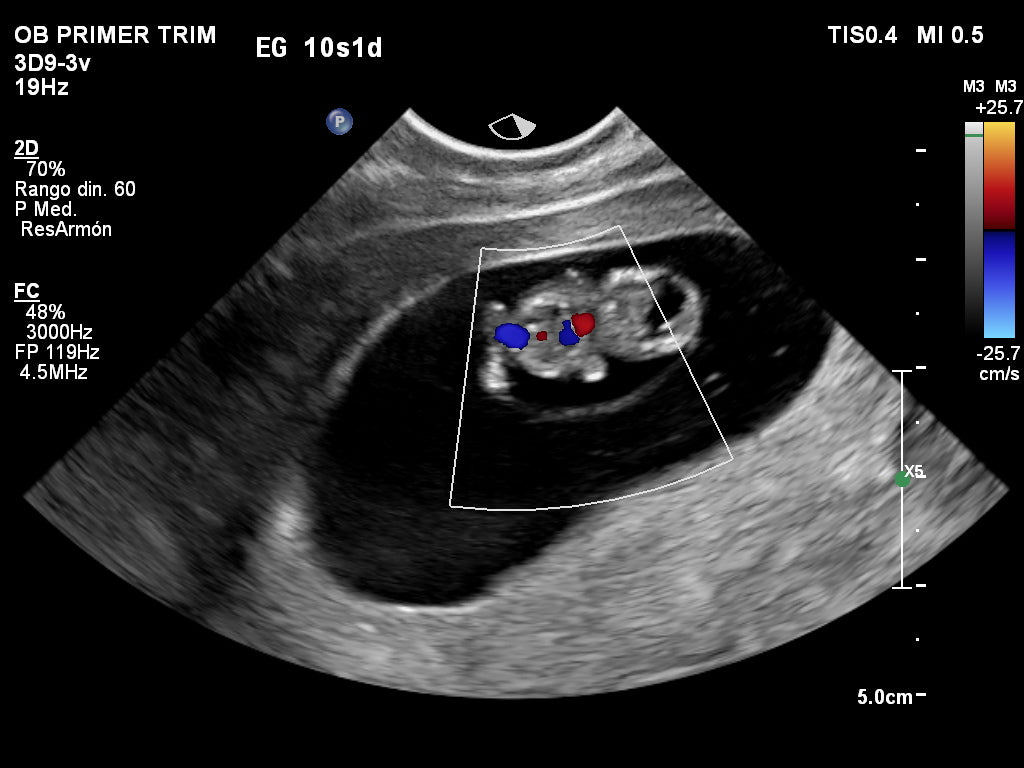

Transvaginal 6D

Realizarlo entre las 5 a 10 semanas.

Disfruta y llévate grandes recuerdos con las maravillosas imágenes de tu bebé en sus primeras semanas, La tecnología GlassVue nos muestra impresionantes tomas sobre el saco gestacional, el embrión y detección de hematomas u otras patologías incipientes.

| Transvaginal de viabilidad |

| 6D | Obtener imágenes de la estructura del embrión a color con volumen, en lugar de imágenes planas en tiempo real aportando una mayor capacidad de diagnóstico y por otro lado se ha demostrado el alto impacto que genera en el vínculo materno fetal. |